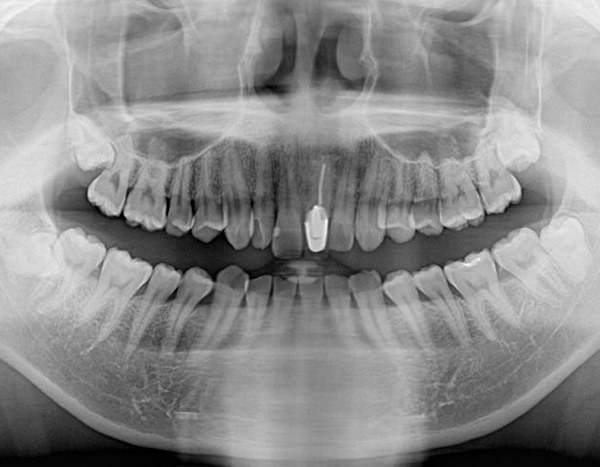

短時間で安全に親知らずを抜歯するためには、事前の画像検査が欠かせません。CT撮影により、親知らずや顎の骨の状態を詳しく知ることができます。その上でお口の中を拝見します。現状と歯科医としての意見をお伝えし、患者様と話し合いながら、抜歯を行うのか、残して経過観察に留めるか決定します。